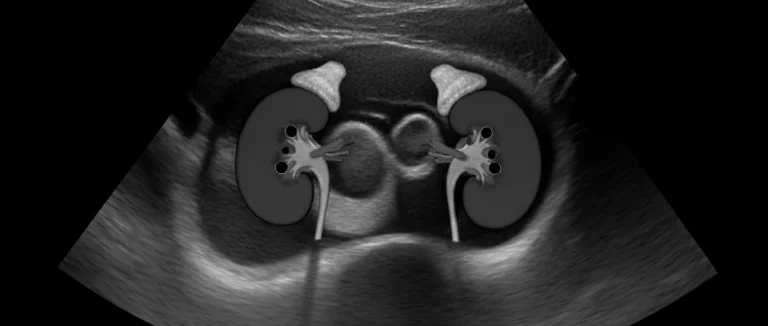

Для уточнения причины у конкретного ребёнка часто проводят ультразвуковое исследование почек и мочевого пузыря, а также уродинамическое исследование при подозрении на анатомические аномалии.

- Визуализационные методы: ультразвуковое исследование (УЗИ) почек и мочевого пузыря, при необходимости – компьютерная томография (КТ) без контраста.